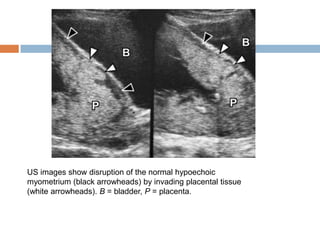

   Sonographic features of placenta accreta include

 loss of the normal retroplacental clear space,

 anomalies of the bladder-myometrium interface,

 prominent placental lacunae, and

 increased vascularity at the interface of the uterus and

bladder .

   Of these various sonographic features, the

presence of prominent placental lacunae has the

highest positive predictive value. Lacunae are

characterized by ill-defined margins, irregular

shape, and turbulent flow.

US images show disruption of the normal hypoechoic

myometrium (black arrowheads) by invading placental tissue

(white arrowheads). B = bladder, P = placenta.

US images showdisruption of the normal hypoechoic myometrium (black arrowheads) by invading placental tissue (white arrowheads). B = bladder, P = placenta.